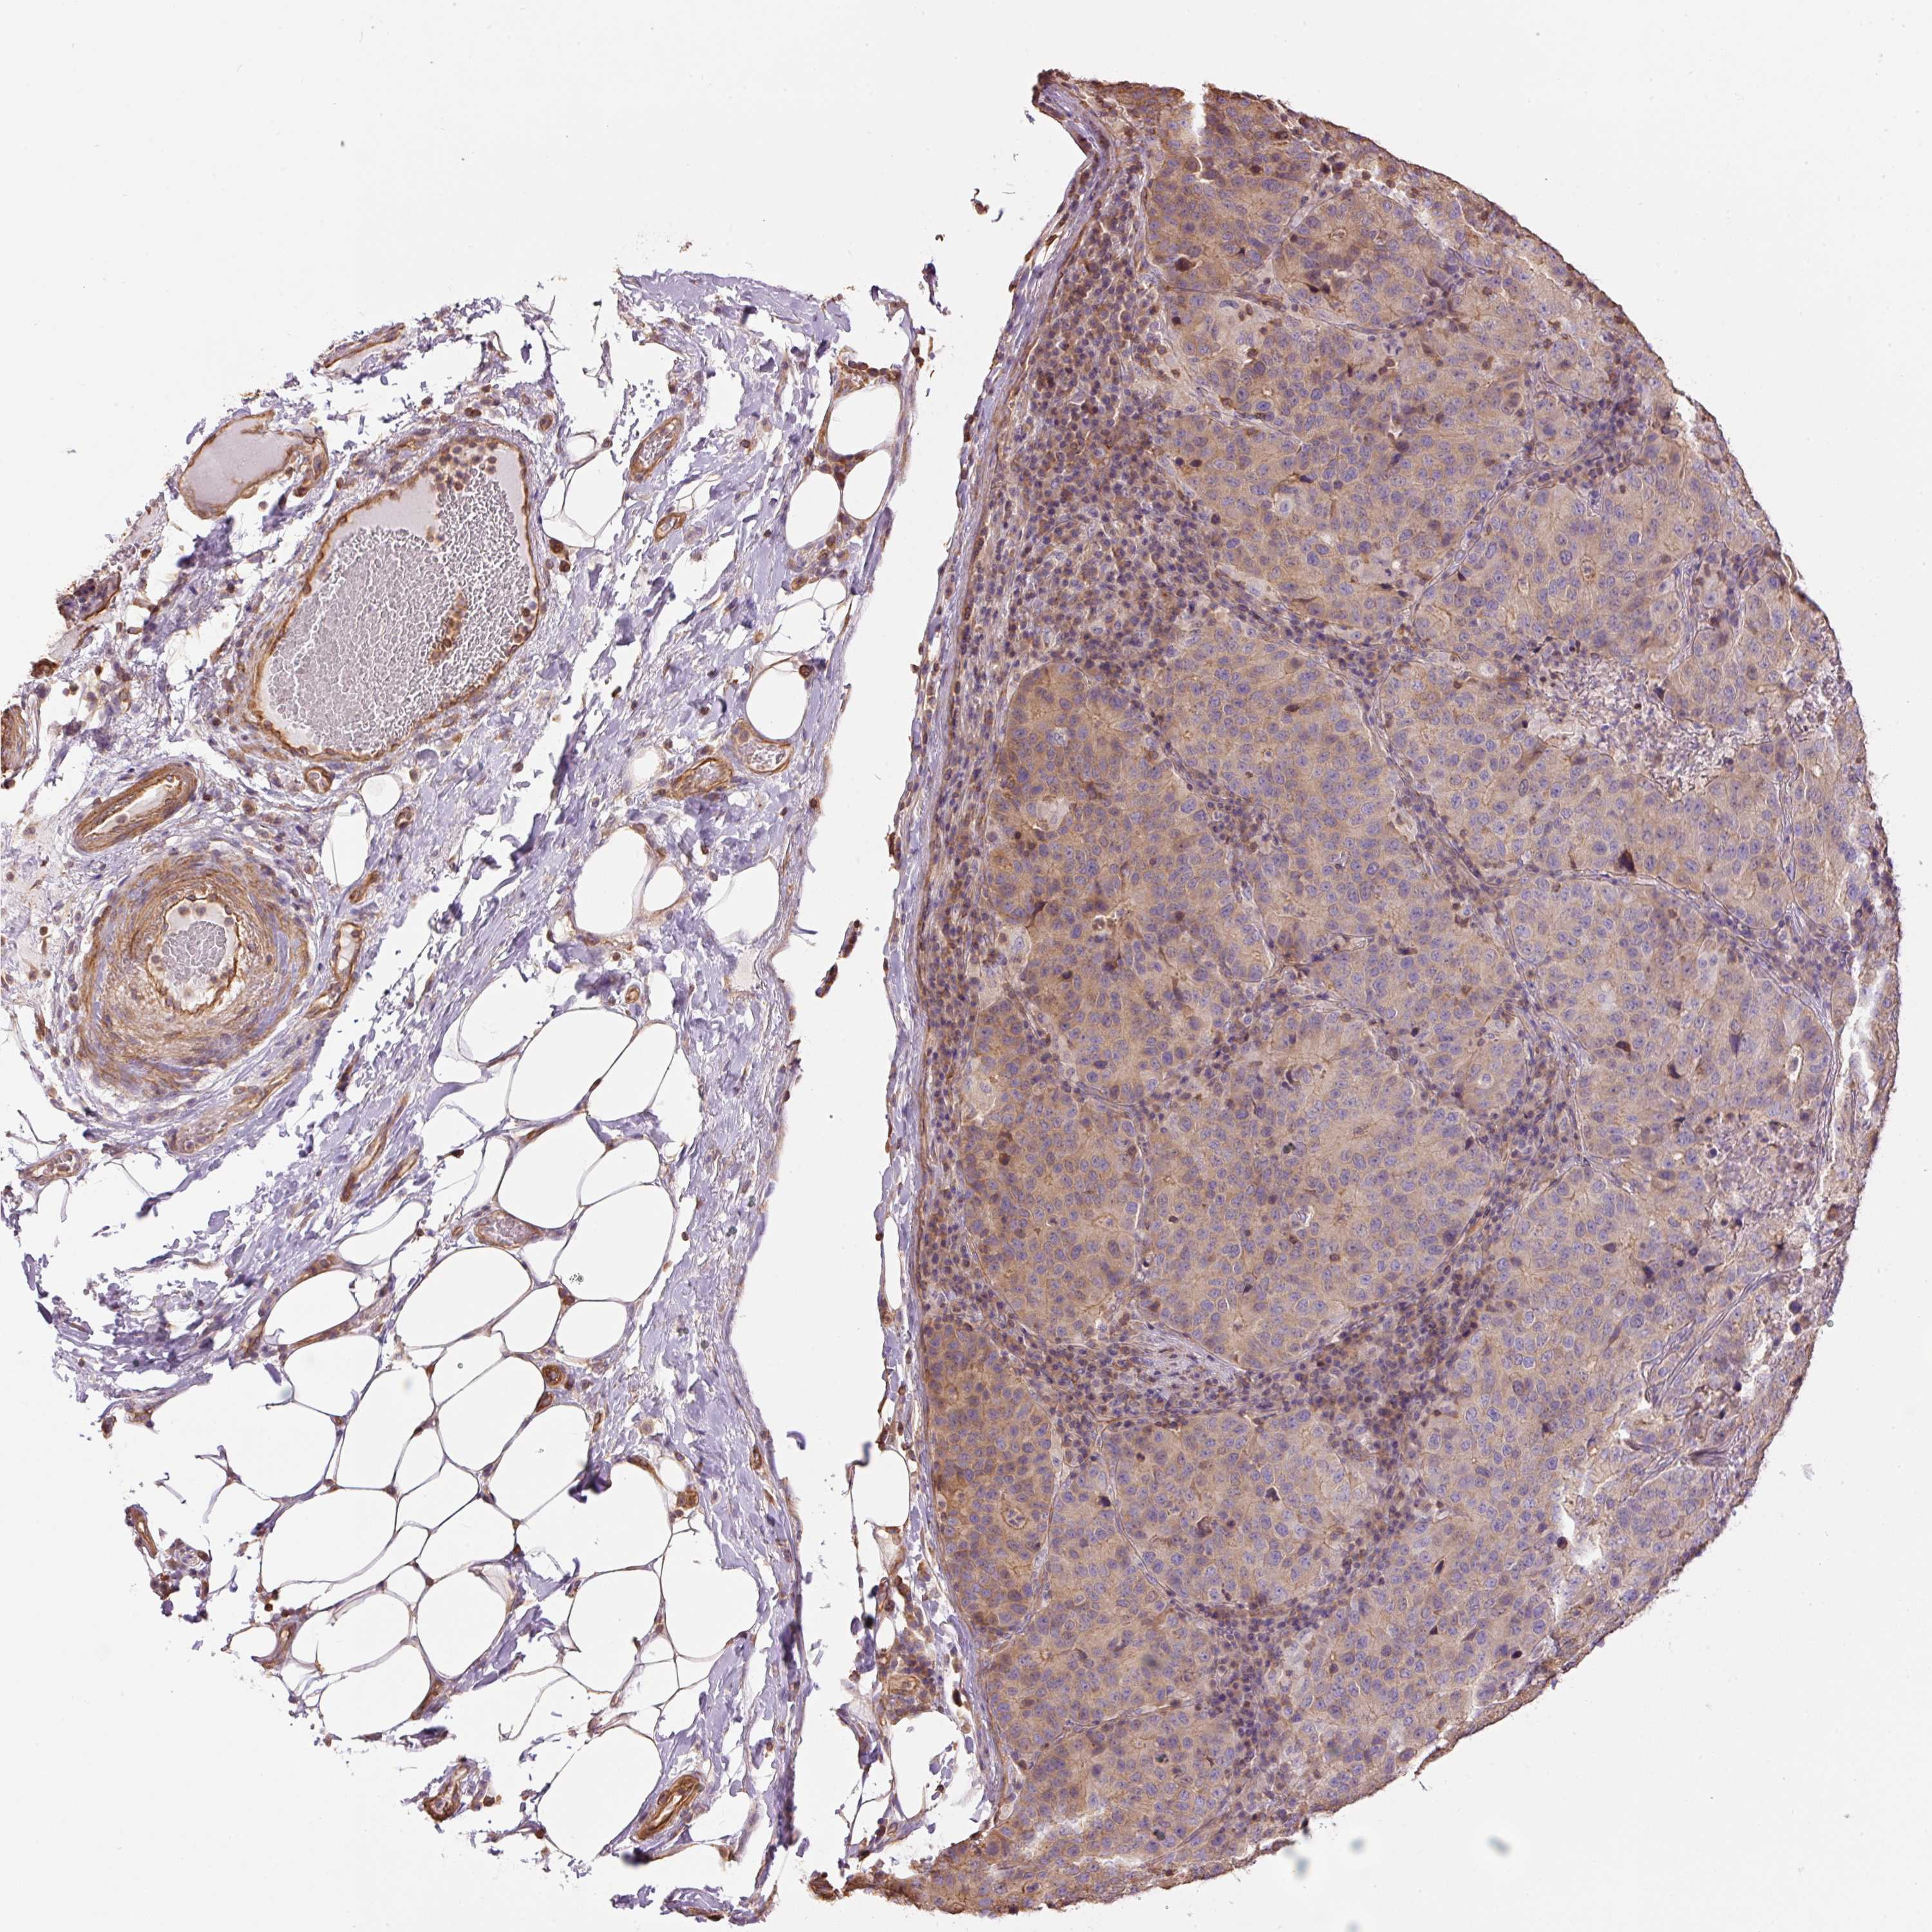

STOMACH CANCER - Protein expressioni

A mouse-over function shows sample information and annotation data. Click on an image to view it in a full screen mode. Samples can be filtered based on level of antibody staining by selecting one or several of the following categories: high, medium, low and not detected. The assay and annotation is described here.

Note that samples used for immunohistochemistry by the Human Protein Atlas do not correspond to samples in the TCGA dataset.

Antibody stainingi

Antibody staining in the annotated cell types in the current human tissue is reported as not detected, low, medium, or high, based on conventional immunohistochemistry profiling in selected tissues. This score is based on the combination of the staining intensity and fraction of stained cells.

Each image is clickable and will lead to virtual microscopy that enables deeper exploration of all samples and also displays staining intensity scores, fraction scores and subcellular localization as well as patient and tissue information for each sample.

Antibody HPA048630

Antibody HPA061142

Antibody CAB004026

Staining

High

Medium

Low

Not detected

Intensity

Strong

Moderate

Weak

Negative

Quantity

>75%

75%-25%

<25%

None

Location

Nuclear

Cytoplasmic/membranous

Cytoplasmic/membranous,nuclear

Adenocarcinoma, NOS

Adenocarcinoma, High grade